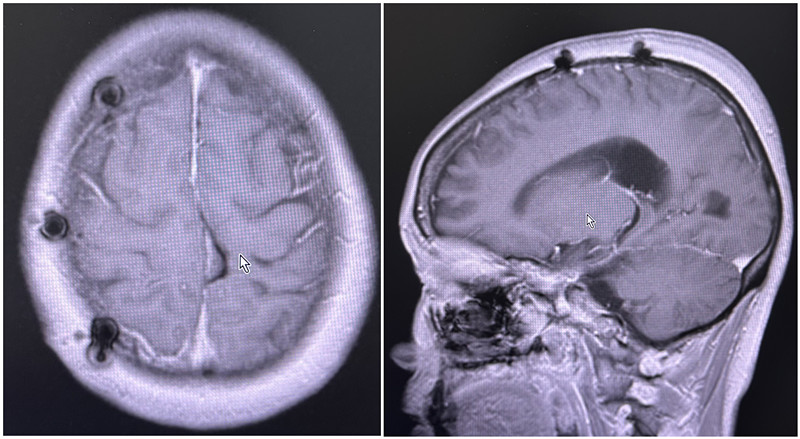

患者术后核磁共振影像

三、术后康复:术后八个月随访无复发,患者重获健康

术后,在神经外科医护团队的精心护理下,梁女士恢复顺利,左手麻木症状逐渐缓解。截至2025年7月,术后八个月的随访检查显示,梁女士脑部影像未见肿瘤复发迹象,肢体功能较前恢复,日常生活已回归正常。